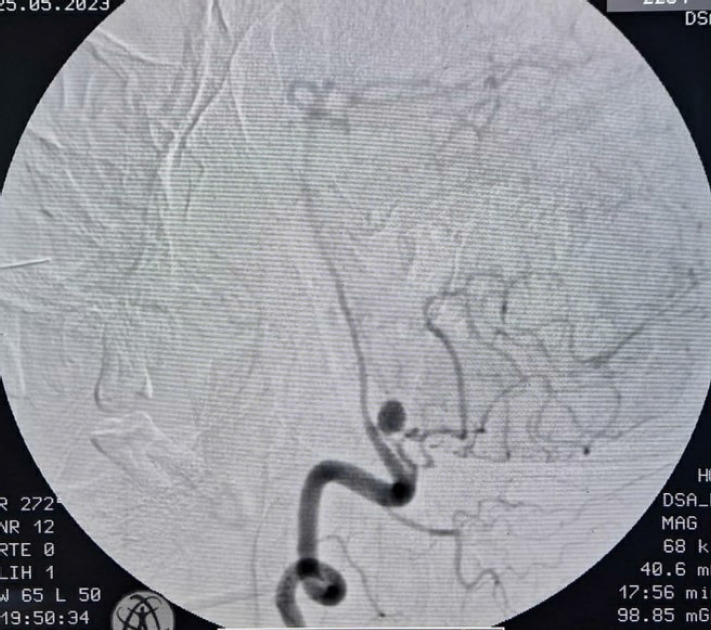

Percutaneous techniques for femoral arterial access are increasingly being performed due to advances in endovascular cerebral procedures, as they provide a less morbid and minimally invasive approach than open procedures. Common complications associated with this peripheral puncture include hematoma, bleeding, pseudoaneurysm, arteriovenous fistula, retroperitoneal bleeding, inadvertent venous puncture, dissection, etc. The retrograde femoral access is currently the most frequently used arterial access as it is technically straightforward, allows for the use of larger size sheaths and catheters, allows repeated attempts, etc. Although being technically less challenging, grave complications can occur due to hardware failure. Here, we present a case of unruptured posterior inferior cerebellar artery (PICA) aneurysm, who underwent uneventful diagnostic cerebral digital substraction angiography (DSA) via right femoral artery route on first attempt, but on second attempt for therapeutic intervention, landed up with stuck guide wire and faced decannulation difficulty due to unravelling of guide wire and multiple knot formation, which was finally removed after multiple attempts at pulling and improvised manoeuvres. Such cannulation and decannulation difficulties have been reported multiple times for central venous access, but extremely rarely for femoral routes, making this case a rarity and worth reporting.